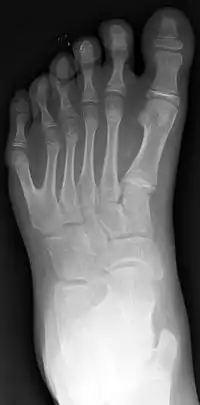

La polidactilia (del griego poly, ‘muchos’ y daktylos, ‘dedo’) es un trastorno genético donde un humano nace con más dedos en la mano o en el pie de los que le corresponde (normalmente un dedo más). Se detecta en el momento del nacimiento. A estos dedos se les llama «dedos extra» o «dedos supernumerarios».

La polidactilia afecta a la mano o al pie en diferentes formas, pero no es una malformación que afecte a la salud de la persona aunque, en algunos casos, puede estar asociada a una anomalía genética más seria en la que pueden existir otras malformaciones físicas.

El dedo adicional es generalmente un pequeño pedazo de tejido fino y suave. A veces contiene el hueso sin articulaciones; ocasionalmente el dedo se encuentra completo y funcional. El dedo extra suele ubicarse tras el meñique de la mano o del pie, es menos frecuentemente del lado del pulgar e inusualmente intercalado entre otros dedos. Suele ser una bifurcación de un dedo normal, y rara vez nace de la muñeca como los demás dedos.